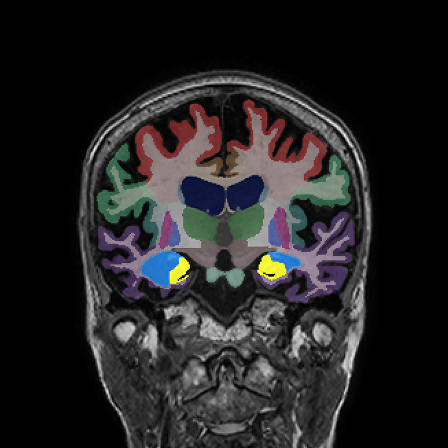

Retrospective brain volumetric analysis in a female patient diagnosed with Alzheimer’s disease at age 77 showed progressive brain atrophy over a 5-year period. The scans demonstrate both hippocampal volume loss and a clear left–right asymmetry.

Hippocampi

Inferior lateral ventricles

Age 72

Age 76

Age 77

Whole brain